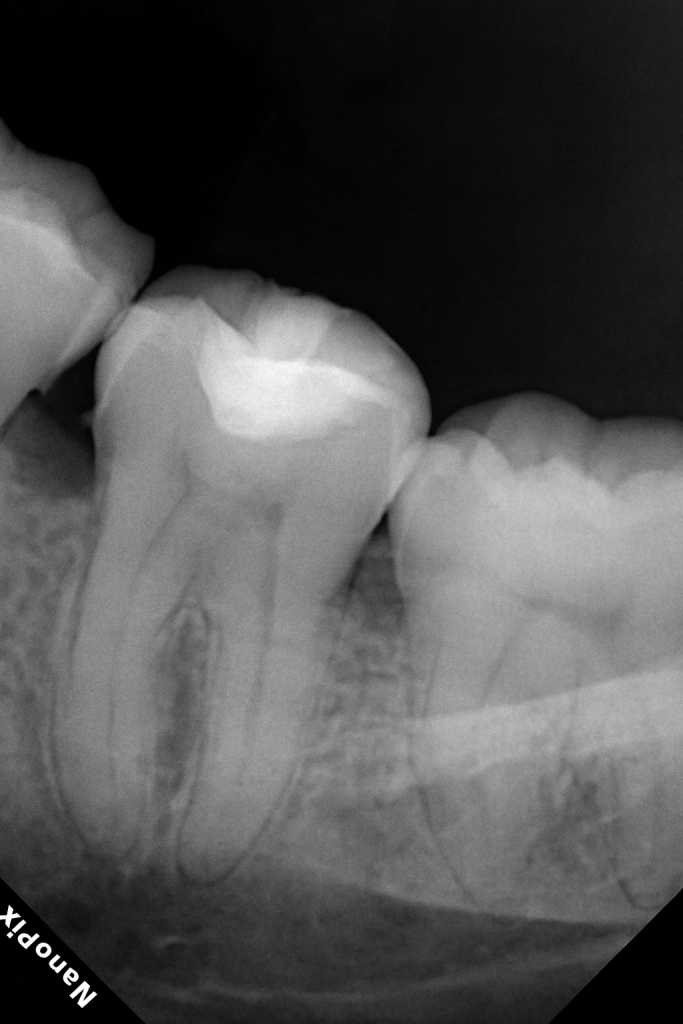

A posterior molar presented with primary occlusal caries confined to enamel and dentin (Fig 1). Under rubber-dam isolation, caries was removed conservatively using a round bur and spoon excavator, preserving peripheral enamel. The cavity design was limited to the carious lesion with no additional mechanical extension.

- Fig 1: Pre-operative view showing occlusal caries.